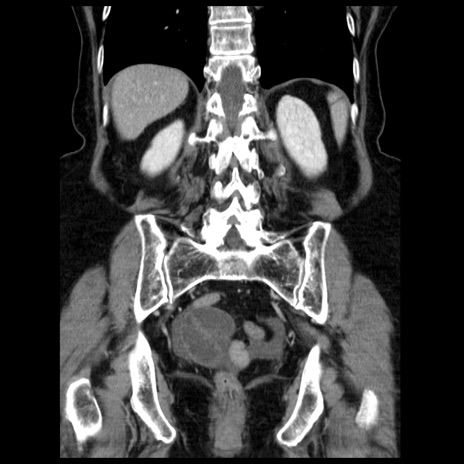

症例13(冠状断像)

【症例】70歳代女性

【主訴】腹痛、嘔吐

【現病歴】15時間程前(昨晩)より腹痛あり。今朝になっても症状の改善なく、嘔吐あり。腹痛も増悪あり、救急外来受診。

【既往歴】子宮癌全摘術後

【身体所見】意識清明、BP 121/72mmHg、P 74bpm、SpO2 100%(RA)、腹部:平坦・軟、腸雑音ほぼ聴取せず。下腹部・心窩部・臍左上に圧痛あり。反跳痛なし。

【データ】WBC 10600、CRP 0.15